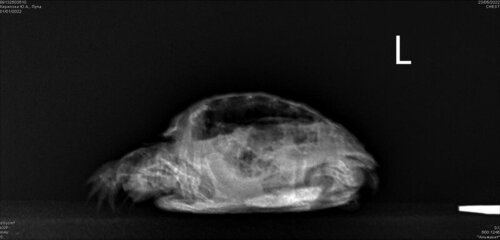

Mister.G Ваше имя: Глеб Локация: Россия, Барнаул Опубликовано: 23 мая 2022 Автор Опубликовано: 23 мая 2022 @moth

Консультанты moth Ваше имя: Мария Локация: Москва Опубликовано: 27 мая 2022 Консультанты Опубликовано: 27 мая 2022 @Mister.G если внутри какая-то стойкая инфекция, то вот так дистанционно сложно определить когда заканчивать курс антибиотика скорее всего не долечили, нужно было ещё дольше колоть лечение пока будет только для той, что делали рентген по второй точно также нужно сделать рентген сначала, прежде чем назначать антибиотики и ингаляции потому что помимо пневмонии у него ещё непонятное воздушное пространство на рентгене, и это не лёгкое и не желудок. Врач очень надеется, что просто газы в петле кишки. Также и у второго черепашонка может быть не пневмония, а те же газы, которые влияют на аппетит и активность.